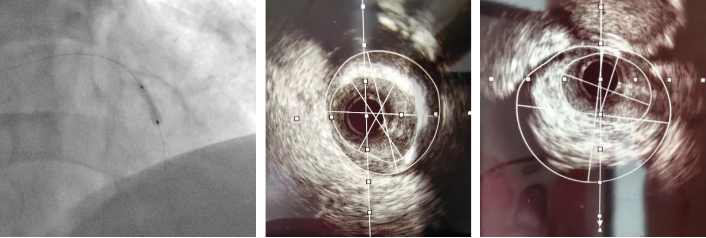

切割扩张后

考虑到目前传统“冠脉内旋磨技术”无法有效解决冠脉深层钙化病变,仔细评估患者病情与适应症后,楚天舒主任当机立断决定使用“Shockwave IVL”新技术处理复杂钙化病变。

Shockwave IVL 是建立在碎石原理的基础上,通过冲击波来碎裂钙化,低压球囊传递冲击波,在安全穿过软组织的同时碎裂浅层和深层血管钙化,使钙化病变松解又不影响血管内膜的完整性,达到钙化斑块修饰的效果,扩大管腔面积的治疗方法。Shockwave IVL为后续的支架顺利置入和展开提供充分的管腔条件,也弥补了目前对于严重钙化病变预处理技术的一些不足。